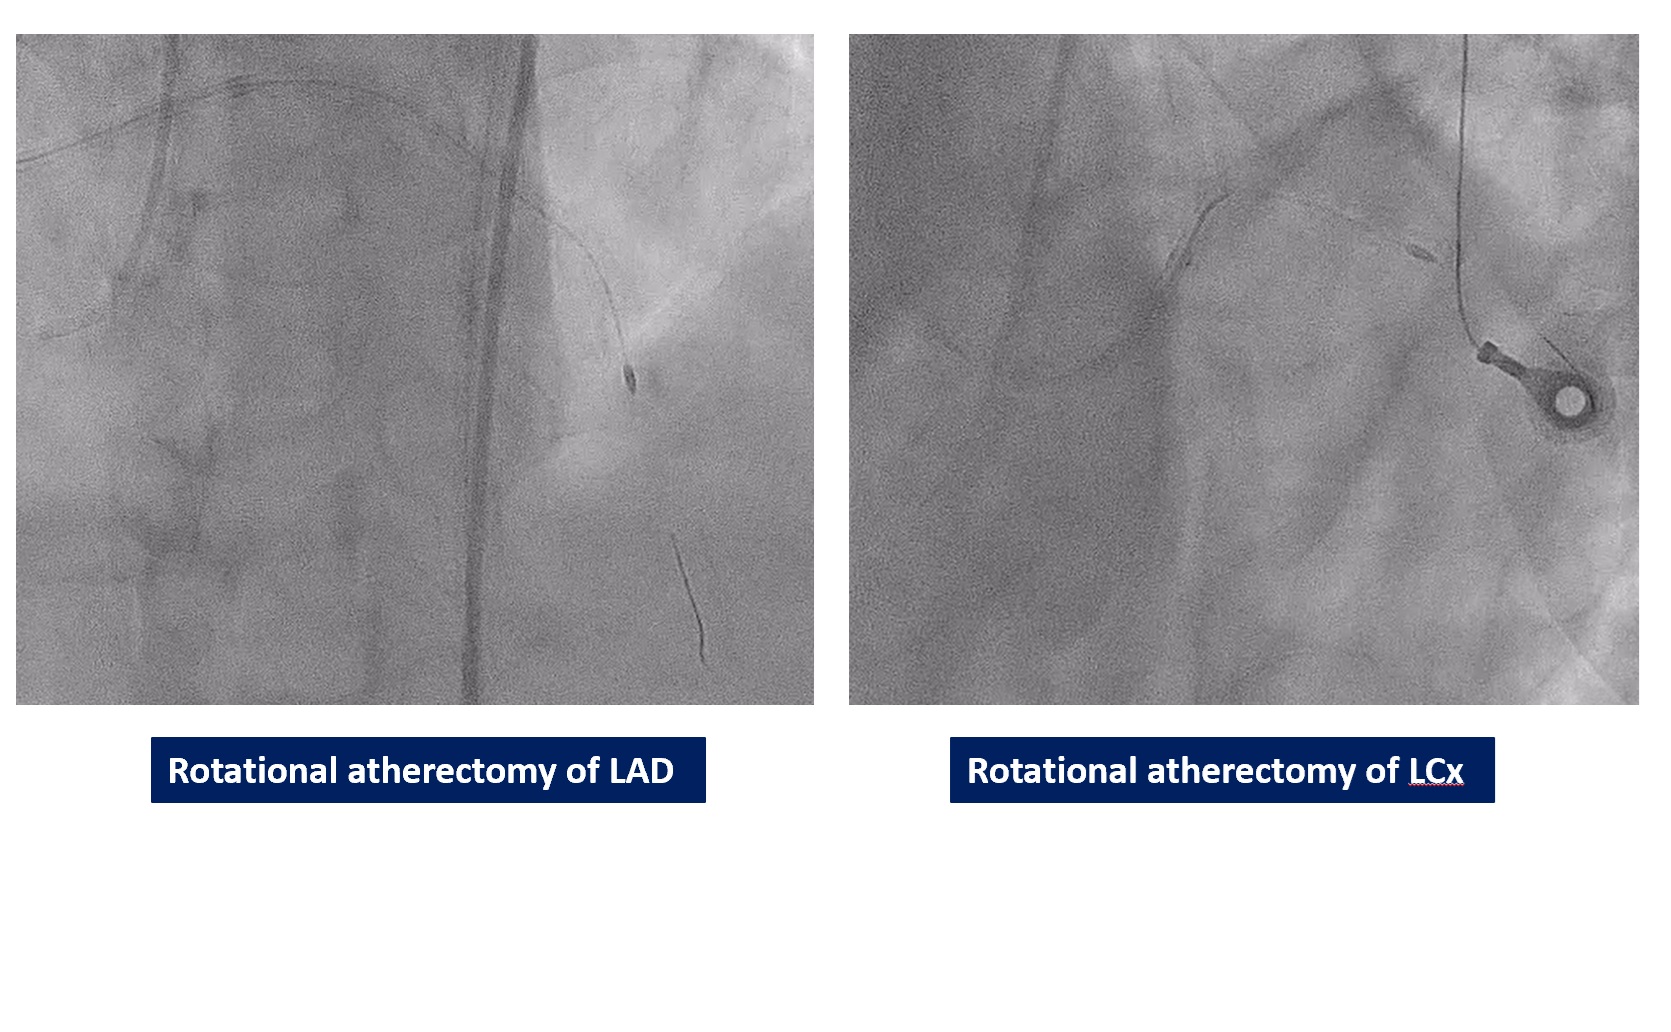

We performed PCI at CTO LAD and LCx with contralateral injection with antegrade wiring and upfront rotablation at LM, LAD and LCx due to heavily calcified lesion. The 7 Fr EBU 3.5 and 6 Fr JR 4.0 catheter were engaged into LCA and RCA, respectively. We opened the LCx CTO segment using microcatheter with Fielder XT guidewire (GW) then rewire from LCx to distal LAD. The CTO GW was exchange to RotaWire Floppy. Rotablation was done at LM-mid LAD with Burr 1.5 mm and LM-proximal LCx with Burr 1.5 mm. IVUS showed EEL of mid LAD = 2.5 mm, proximal LAD = 4.0 mm, distal LM = 5.5 mm and proximal LCx = 3.5 mm. The lesion of mid LAD was prepared with scoring balloon 2.0/15 mm and LM-proximal LAD with scoring balloon 3.5/15 mm. A 2.5/33 mm stent was deployed from proximal-mid LAD. We decided to stenting the lesion at proximal LCx before stenting the lesion at LM-proximal LAD using provisional one stent and POT-kiss-POT technique. A 3.0/26 mm stent was deployed at proximal LCx. A 3.5/38 mm stent was deployed from distal LM-proximal LAD and 3.5/13 mm stent from ostial LM-distal LM. POT was done with a non-compliance (NC) 5.0/12 mm balloon along LM stent. Kissing balloon inflation with NC 3.0/15 mm balloon at LM-LCx and 3.5/15 mm balloon at LM-LAD then final POT with NC 5.0/12 mm was done. IVUS showed well stent expansion, no malapposition and no stent edge dissection. The patient had no re-admission. Echocardiography after 3 months showed significant improvement of LV function to 56%.

The primary treatment for complex coronary artery disease was traditionally coronary artery bypass graft (CABG) surgery. However, complex percutaneous coronary intervention (PCI) is now a feasible option that can achieve good results, especially in patients who are unsuitable for surgery. This case successfully demonstrates a highly complex PCI used to treat a double chronic total occlusion (CTO). The procedure, which involved rotational atherectomy of both the LAD and LCx arteries in a high-risk patient, achieved excellent results without any complications, thus confirming the utility of advanced PCI strategies.